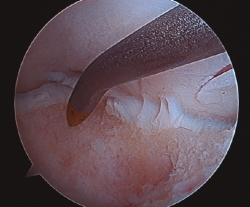

Figura 1. Lesión osteocondral de grado IIB en vertiente talar medial.

- Inicialmente procedemos a retirar el cartílago inestable, el hueso necrótico y la capa superior calcificada mediante un sinoviotomo, fresa motorizada, junto con instrumental de curetaje artroscópico (Figura 1).